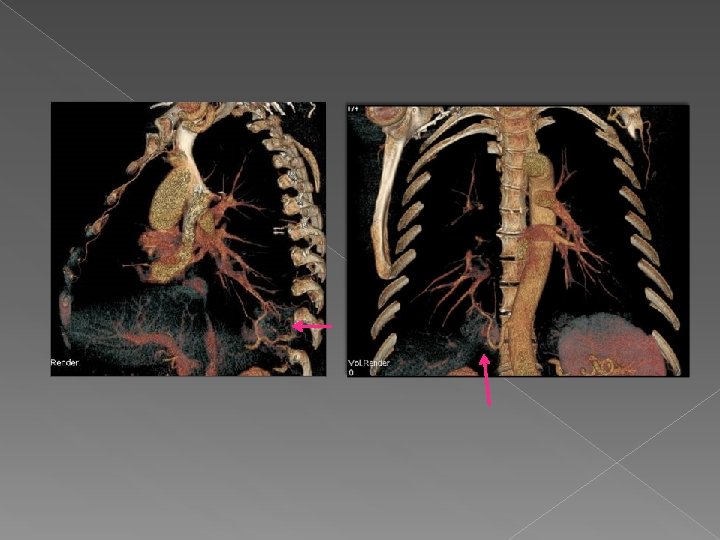

Valor de VR : se visualiza la arteria aferente que se origina en

Valor de VR : se visualiza la arteria aferente que se origina en la aorta y se dirige a la masa con un drenaje venoso a la vena pulmonar inferior derecha. Hallazgos sugestivos de secuestro pulmonar intralobar.

Drenaje venoso Secuestro pulmonar